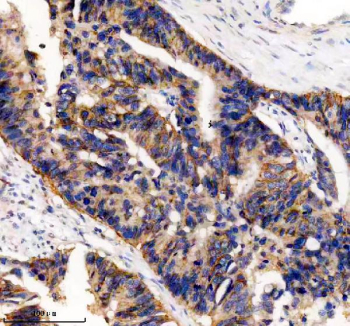

IHC analysis of UBE2A/UBE2B using anti-UBE2A/UBE2B antibody. UBE2A/UBE2B was detected in a paraffin-embedded section of human colon cancer tissue. Heat mediated antigen retrieval was performed in EDTA buffer (pH 8.0, epitope retrieval solution). The tissue section was blocked with 10% goat serum. The tissue section was then incubated with 2 ug/ml rabbit anti-UBE2A/UBE2B antibody overnight at 4oC. Peroxidase Conjugated Goat Anti-rabbit IgG was used as secondary antibody and incubated for 30 minutes at 37oC. The tissue section was developed using an HRP secondary and DAB substrate.